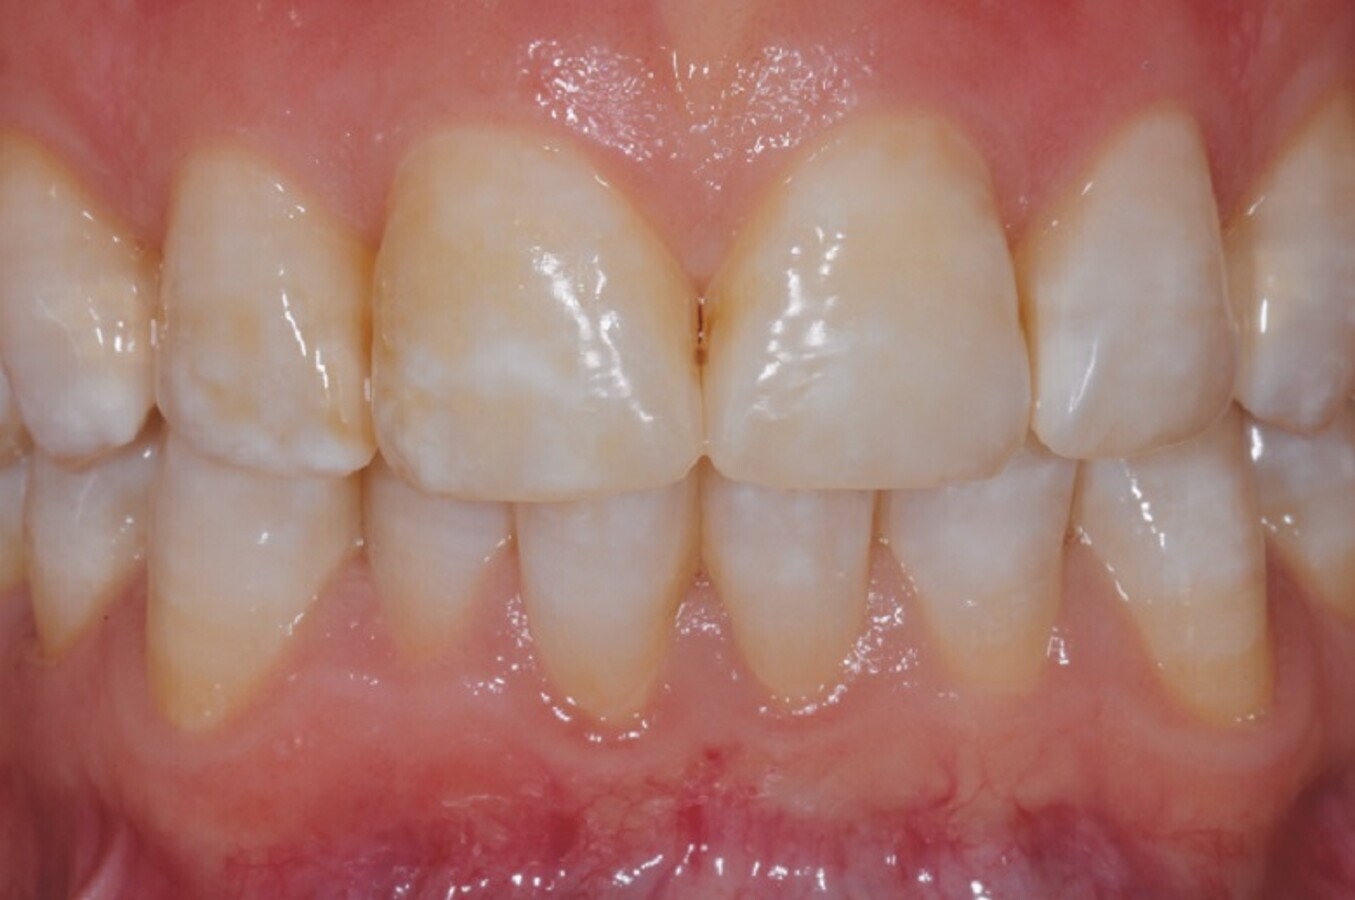

Izboljšanje indeksa zobnih oblog ter zmanjšanje poroznosti zaradi izboljšanja teksture sklenine in dentina po izpostavitvi F-ACP. (Slika: Daniele Modesti)

Pacientka je izkazala visoko stopnjo sodelovanja pri zdravljenju in po predpisanem protokolu, opazila je tudi klinične izboljšave, pa ne le po videzu (fotografiji na slikah 2 in 3 sta posneti po 30 in 70 dneh), temveč tudi glede občutka, tako da je poročala o zmanjšani občutljivosti zob. Pri pregledih lahko opazimo izboljšanje indeksa zobnih oblog ter zmanjšano poroznost zaradi izboljšanja teksture sklenine in dentina.